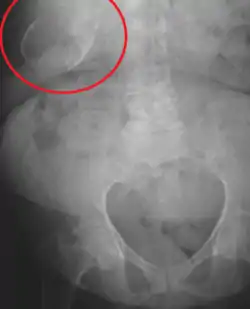

مرارة خزفية

المرارة الخزفية[1] أو تكلس المرارة أو المرارة البورسلانية (بالإنجليزية: Porcelain gallbladder) هو تكلس المرارة الذي يُعتقد أنه ناتج عن الحصى المرارية المفرطة، على الرغم من أن السبب الدقيق غير واضح. وكما هو الحال مع أمراض المرارة بشكل عام، تحدث هذه الحالة في الغالب في المرضى الذين يعانون من زيادة الوزن في منتصف العمر. وهو شكل من أشكال التهاب المرارة المزمن. ويؤدي التندُّب الالتهابي للجدار، إلى جانب تكلس جدار إلى تحويل المرارة إلى وعاء يشبه الخزف، واستئصال المرارة هو العلاج الموصى به.

التصوير الإشعاعي للبطن (بالأشعة السينية)، أو الموجات فوق الصوتية على البطن، أو الأشعة المقطعية.